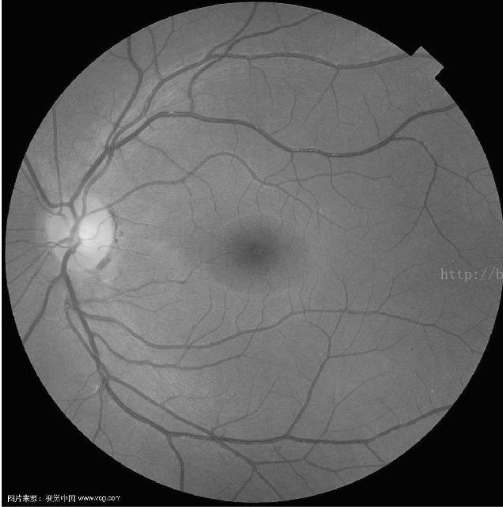

那一副医学图像做测试,效果确实不错:

原图 尺度数量为5,最大尺度为16的结果

同样参数原始作者版本的结果,明显没有maltab的清晰

这个算法我测试确实对血管图像的提取效果比较显著,在贴几个图片。